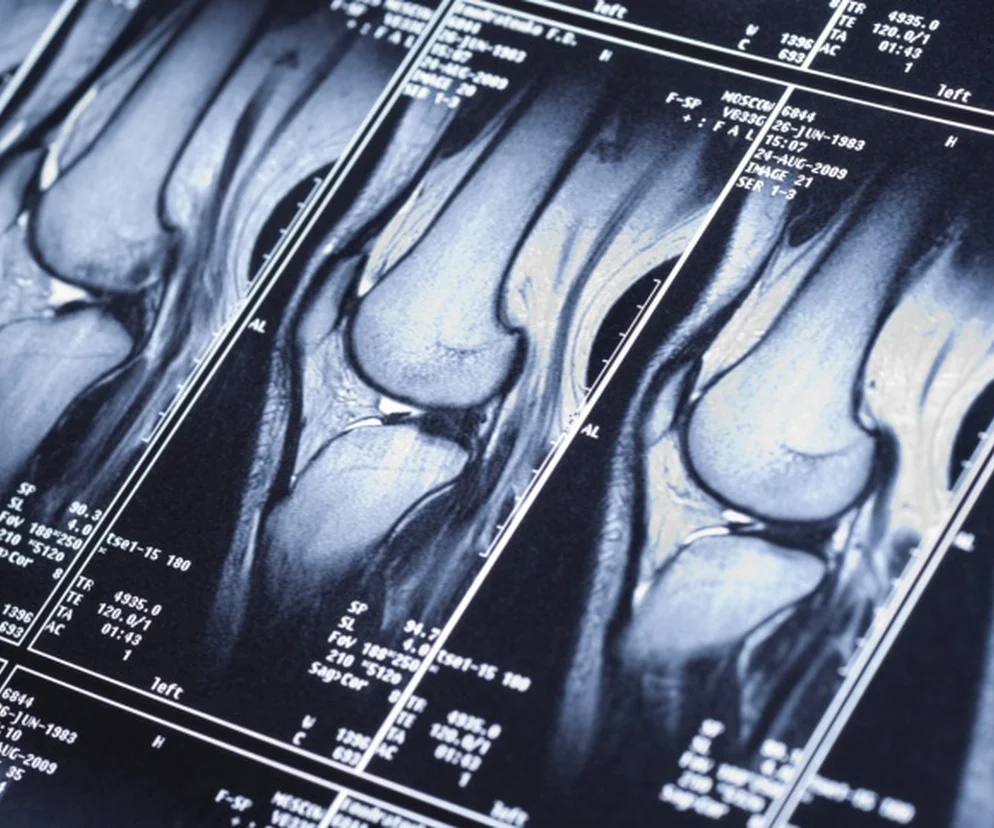

• Aby potwierdzić uraz łąkotki, lekarz przeprowadza tzw. testy łąkotkowe. Później zleca wykonanie USG i rezonansu magnetycznego. Ale wyniki tych badań dopiero w połączeniu z objawami klinicznymi pozwalają na postawienie diagnozy.